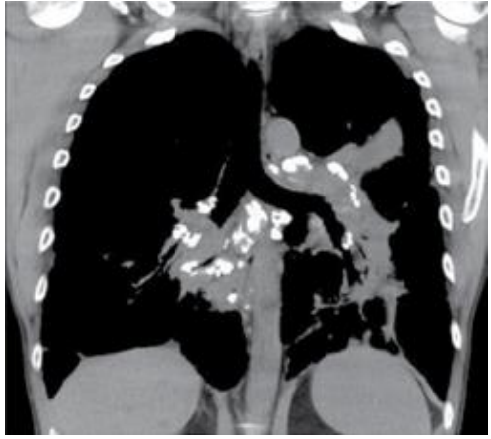

Paciente do sexo feminino, 46 anos, sem histórico de tabagismo, queixando-se de tosse seca e cansaço. A paciente realizou tomografia computadorizada como parte da rotina diagnóstica.

Os achados radiológicos típicos da sarcoidose incluem pequenos nódulos com distribuição perilinfática, opacidades parenquimatosas bilaterais perihilares e alterações fibróticas.